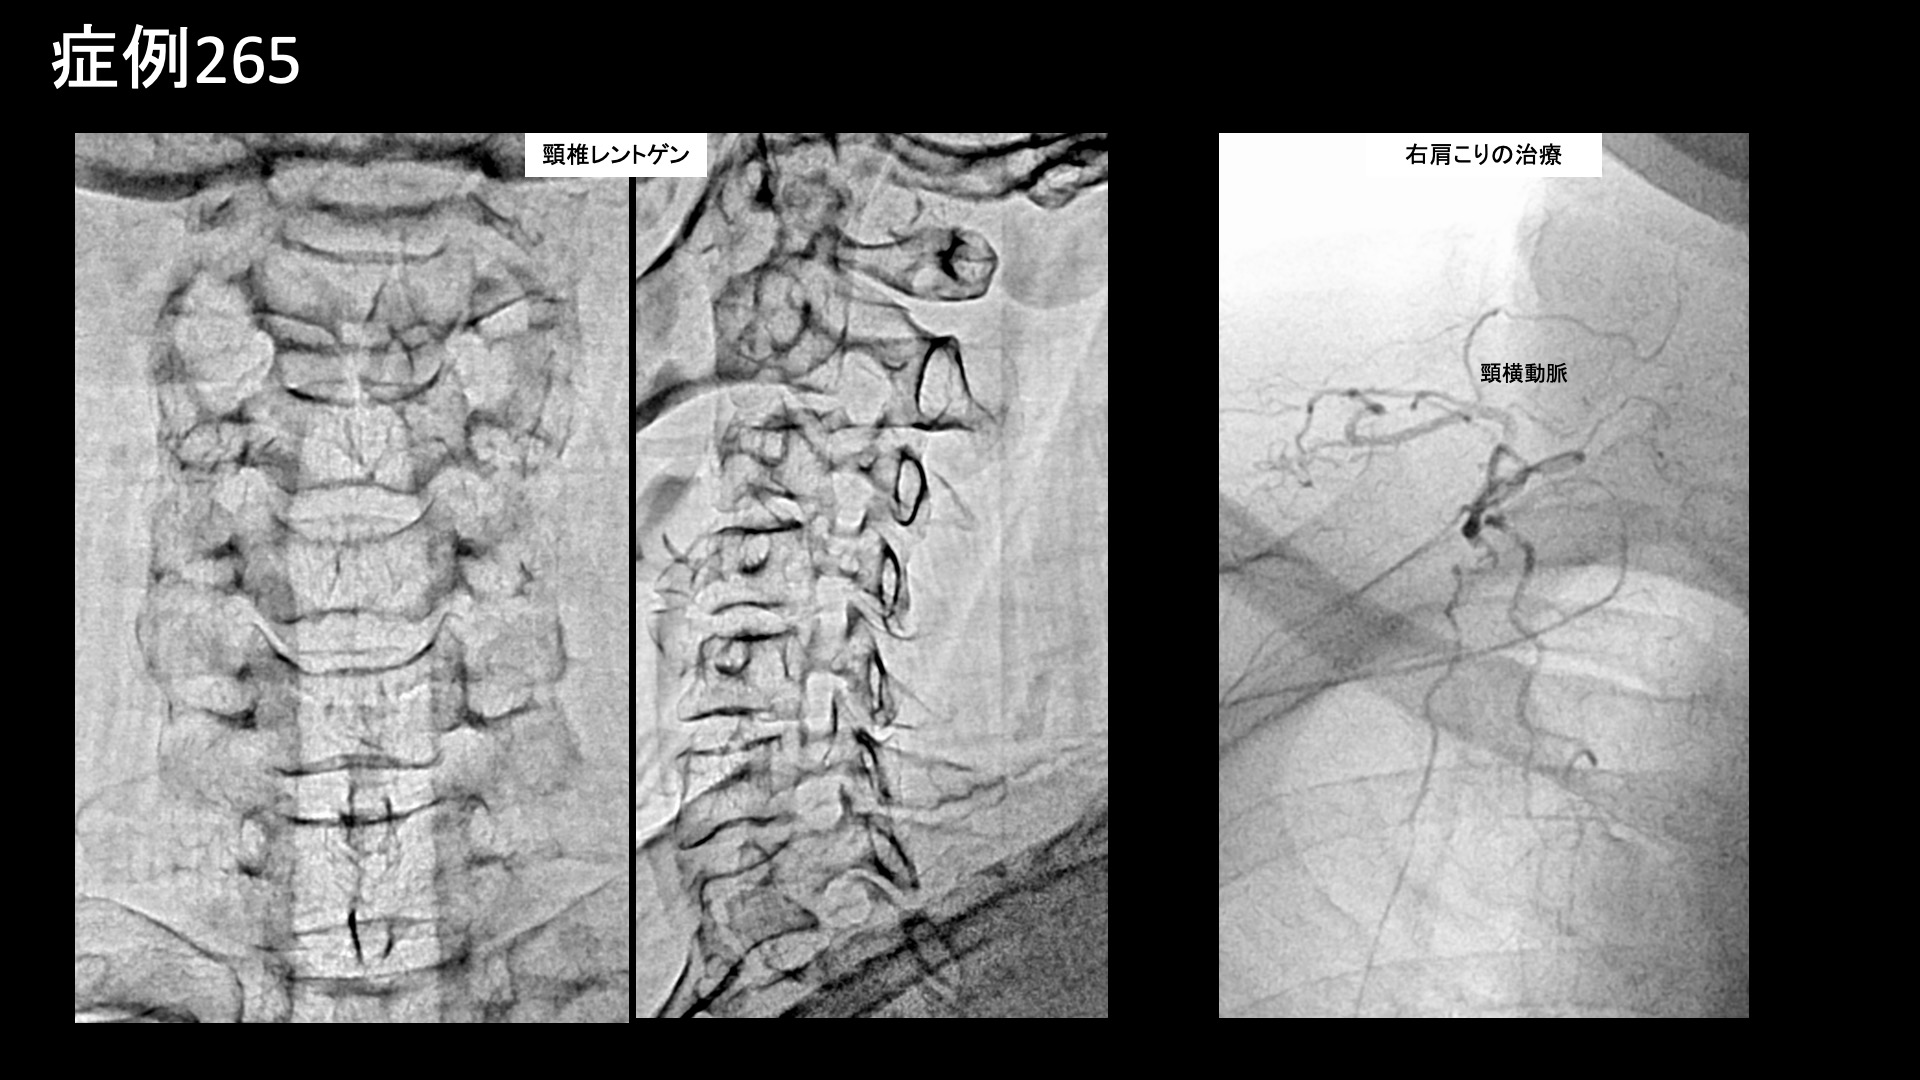

首の可動域を確認すると、側屈や回旋動作で中等度以上の制限がみられました。頸椎椎間関節や肩甲骨周囲に圧痛を認めました。触診では、こりの重症度は最重症レベルでした。エコー検査では、僧帽筋周囲組織の線維化が左側優位に進行していました。レントゲンでは、頸椎は保たれているものの、後頸部の項靭帯の石灰化を認めました。頸椎症は否定的であり、首肩こり(頸肩腕症候群)の診断でモヤモヤ血管の治療適応と判断し、モヤモヤ血管(病的新生血管)に対する運動器カテーテル治療(微細動脈塞栓術)を受けていただきました。

血管造影を行うと、首こりの主要責任血管である深頸動脈で、左側優位にモヤモヤ血管が濃染像として描出されました。治療後は画像上速やかに消失しました。その他肩こりの血管など複数箇所の治療を行い終了しました。